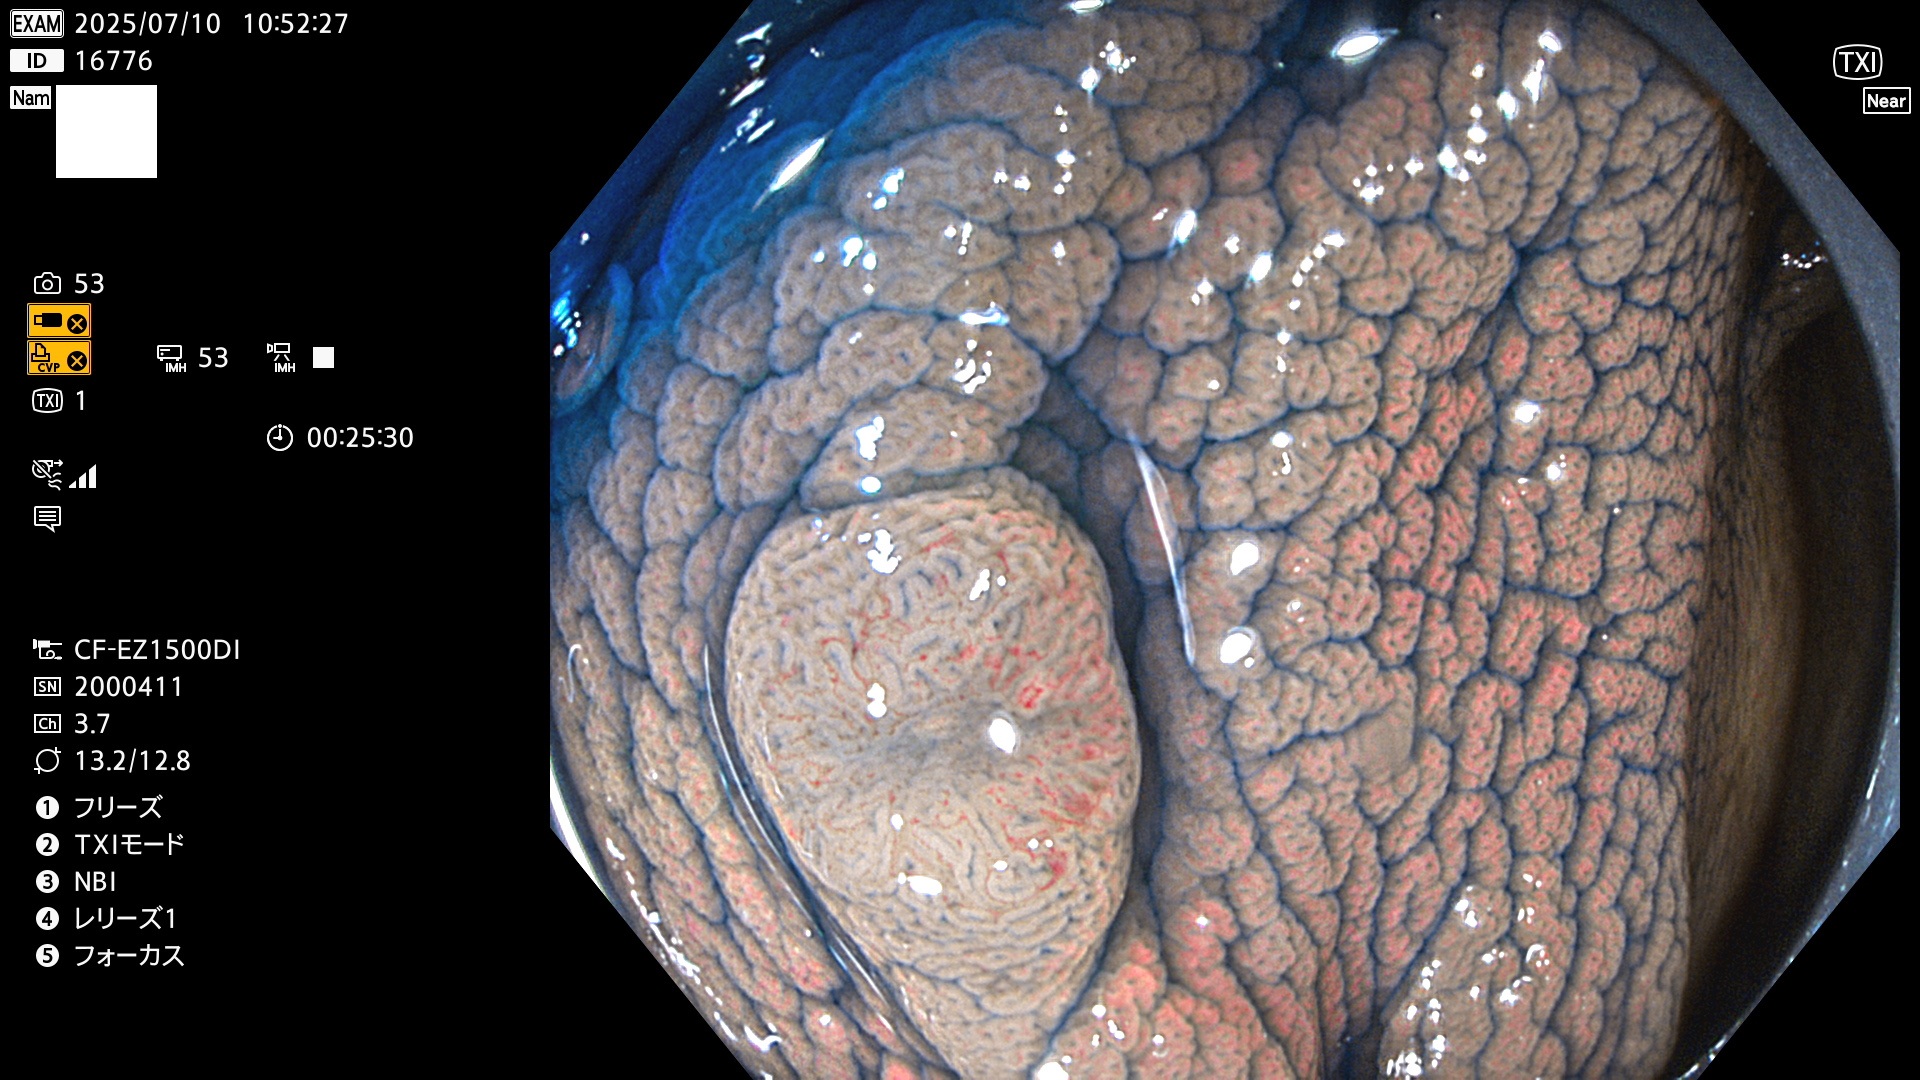

2025年7月10日〜7月13日の4日間(40件)15個 (Uc_ADR=15/40=38%)